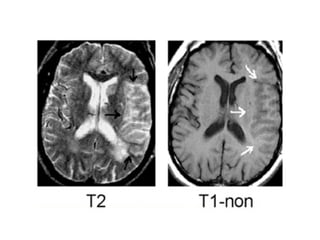

NECT shows hyperdense internal veins and bilateral (R > L) thalami

hypodensities , compatible with dural vein thrombosis and venous

T1 revealing swollen hypointense thalami , T2 depicting swollen hyperintense

thalami

FLAIR image demonstrating high signal in the left thalamus , there is also high

signal in the basal ganglia on the right, these bilateral findings should raise

the suspicion of deep cerebral venous thrombosis, a sagittal CT

reconstruction demonstrates a filling defect in the straight sinus and the

vein of Galen (arrows)

Bilateral abnormalities in the region of the basal ganglia, based on the imaging findings there is a broad

differential including small vessel disease, demyelination, intoxication and metabolic disorders, but there

are abnormal high signal in the internal cerebral veins and straight sinus on the T1, where there should be

a low signal due to flow void, this was unlike the low signal in other sinuses, diagnosis is bilateral

infarctions in the basal ganglia due to deep cerebral venous thrombosis